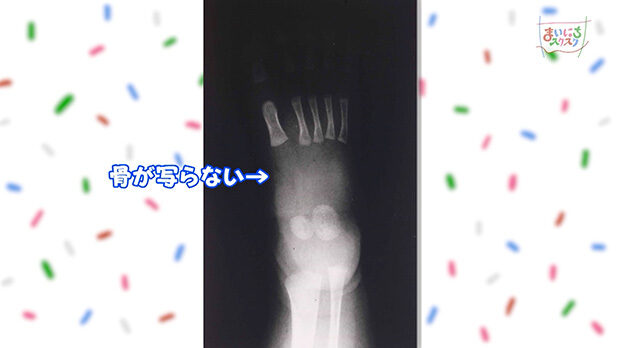

生まれたばかりの赤ちゃんの足のX線写真です。軟骨の部分が多いため、骨がはっきりと写りません。大人とほぼ同じように骨が写るようになるのは6歳ごろです。

まだ関節がゆるく、足全体が軟らかいため、合っていない靴でも履けてしまいます。一方で、外からの衝撃に弱く、簡単に変形してしまうため注意が必要です。